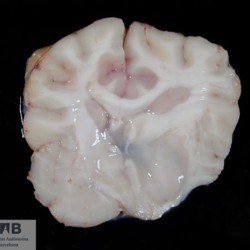

Pàgina anterior de 637 Pàgina següent 3181 total Canine Specie: Canine Organ: Brain Lesion: Glioma Lesion modifier: - Disease: - Files/Expedient: N-338/09 Not viewed Canine Specie: Canine Organ: Brain Lesion: Glioma Lesion modifier: - Disease: - Files/Expedient: N-338/09 Not viewed Feline Specie: Feline Organ: Spinal cord Lesion: Lymphoma Lesion modifier: - Disease: - Files/Expedient: N-331/09 Not viewed Equine Specie: Equine Organ: Brain Lesion: Malacia Lesion modifier: - Disease: - Files/Expedient: N-294/05 Not viewed Equine Specie: Equine Organ: Brain Lesion: Malacia Lesion modifier: - Disease: - Files/Expedient: N-294/05 Not viewed Pàgina anterior de 637 Pàgina següent Títol Select...Avian (Exotic) (110)Avian (Poultry) (76)Bovine (317)Canine (935)Caprine (47)Equine (257)Feline (326)Ferret (19)General (127)Marine mammal (22)Non-human primate (20)Ovine (328)Porcine (379)Rabbit (61)Reptile (38)Rodent (28)Wildlife (91) Format Select...- (60)Abomasum (37)Adrenal gland (10)Blood (7)Blood vessel (50)Body as a whole (19)Bone (57)Bone marrow (21)Brain (93)Cloaca (1)Diaphragm (2)Ear (5)Esophagus (39)Eye (16)Fetus (12)Gallbladder (23)Gizzard (2)Heart (265)Intestine (356)Joint (32)Kidney (443)Larynx (5)Liver (326)Lung (264)Lymph node (91)Mammary gland (10)Mediastinum (1)Muscle (22)Nasal cavity (22)Nerve (7)Omasum (5)Oral cavity (63)Ovary (14)Oviduct (8)Pancreas (7)Parathyroid (5)Penis (10)Peritoneum (65)Pharynx (9)Pituitary gland (6)Placenta (7)Prostate (8)Proventriculus (3)Reticulum (1)Rumen (28)Sinus (7)Skin (181)Spinal cord (15)Spleen (105)Stomach (125)Teeth (1)Testicle (11)Thoracic cavity (31)Thymus (13)Thyroid gland (5)Tongue (32)Tonsils (11)Trachea (11)Urethra (5)Urinay bladder (61)Uterus (27)Vagina (1)Vulva (1)Yolk sac (1) Cobertura Select...- (152)Abomasitis (26)Abscess (27)Acidosis (1)Adenocarcinoma (20)Adenoma (9)Aerosacculitis (6)Agenesis (1)Agnathia (1)Alopecia (7)Amyloidosis (12)Aneurysm (6)Angiectasis (1)Anthracosis (1)Arteritis (11)Arthritis (15)Arthrogryposis (6)Artifact (4)Ascites (13)Atelectasis (8)Atherosclerosis (5)Atresia (1)Atrial septal defect (2)Atrophy (10)Autolysis (7)Bronchitis (6)Bronchopneumonia (26)Cachexia (2)Carcinoma (103)Cardiomyopathy (19)Cellulitis (2)Chemodectoma (4)Cholangiohepatitis (4)Cholangitis (19)Cholecystitis (4)Cholestasis (5)Chondrodysplasia (2)Chondrosarcoma (2)Chronic passive congestion (13)Chylothorax (2)Cirrhosis (6)Coelomitis (3)Coenurus cerebralis (4)Colitis (40)Congestion (17)Conjunctivitis (5)Coronitis (3)Cryptorchidism (3)Cyst (25)Cystitis (24)Dermatitis (69)Diaphragmatic hernia (4)Dilation (28)Discospondylitis (1)Disseminated intravascular coagulation (7)Dyschondroplasia (1)Dysplasia (29)Ectopia cordis (1)Ectopic ureter (1)Edema (55)Emphysema (5)Encephalitis (5)Endocardiosis (14)Endocarditis (26)Endometritis (5)Enteritis (118)Enterolith (6)Epulis (3)Esophagitis (14)Fasciitis (1)Fibrosis (7)Fibrous osteodystrophy (8)Fistula (1)Folliculitis (3)Fracture (2)Gastritis (34)Gingivitis (5)Glioma (8)Glomerulonephritis (21)Glossitis (25)Glycogenosis (1)Gout (8)Granuloma (2)Granulosa cell tumor (4)Hemangioma (9)Hemangiosarcoma (46)Hematoma (8)Hemoglobinuria (2)Hemopericardium (12)Hemoperitoneum (2)Hemorrhage (100)Hemosiderosis (7)Hemothorax (2)Hepatitis (78)Hernia (11)Histiocytosis (3)Hydatid cyst (11)Hydrocephalus (9)Hydrometra (1)Hydronephrosis (22)Hydropericardium (6)Hydrothorax (3)Hydroureter (5)Hyperkeratosis (8)Hyperostosis (4)Hyperplasia (37)Hypertrophy (9)Hypopigmentation (1)Hypoplasia (7)Hypopyon (1)Impaction (6)Infarction (63)Insulinoma (6)Intussusception (5)Jaundice (17)Laminitis (2)Laryngitis (2)Leiomyoma (5)Leukemia (13)Lipidosis (36)Lipoma (7)Lymphadenitis (45)Lymphadenopathy (7)Lymphangiectasia (6)Lymphangitis (5)Lymphoma (221)Malacia (11)Malignant melanoma (15)Mast cell tumor (11)Mastitis (8)Megaesophagus (2)Melanosis (3)Melena (4)Meningioma (6)Meningitis (6)Meningocele (2)Meningoencephalitis (5)Mesothelioma (5)Methemoglobinemia (2)Mineralization (10)Mucocele (5)Mucometra (1)Multilobular bone tumor (1)Mummification (3)Myelofibrosis (1)Myocarditis (4)Myositis (5)Necrosis (81)Nephritis (113)Nephroblastoma (6)Nephrosclerosis (1)Nephrosis (14)Neuritis (1)Obstruction (13)Omasitis (4)Omphalitis (1)Omphalophlebitis (7)Orchitis (4)Osteoarthrosis (5)Osteomyelitis (9)Otitis (2)Palatoschisis (3)Pancreatitis (3)Panniculitis (3)Papilloma (7)Parakeratosis (14)Patent ductus arteriosus (6)Peliosis hepatis (1)Perforation (17)Pericarditis (35)Peritonitis (39)Persistent right aortic arch (1)Pharyngitis (2)Pheochromocytoma (2)Phlebitis (2)Placentitis (6)Pleuritis (21)Pleuropneumonia (24)Pneumonia (109)Pneumothorax (3)Polycystosis (14)Polyp (5)Polyserositis (6)Posthitis (1)Proctitis (4)Prolapse (3)Prostatitis (3)Proventriculitis (1)Pyelonephritis (24)Pyometra (6)Pyothorax (4)Rhinitis (11)Rumenitis (6)Rupture (24)Salpingitis (3)Sarcoma (57)Sclerosis (1)Scoliosis (2)Seminoma (2)Sequestrum (2)Serous atrophy (14)Sinusitis (7)Splenitis (14)Splenomegaly (9)Spondylitis (6)Spondylosis (1)Stenosis (9)Stomatitis (32)Tenosynovitis (2)Teratoma (3)Thricobezoar (2)Thrombosis (16)Tonsilitis (4)Torsion (13)Tracheitis (4)Tympany (7)Typhlitis (8)Typhlocolitis (4)Ulcer (43)Urethritis (1)Urolithiasis (36)Uroperitoneum (1)Uveitis (1)Vasculitis (15)Ventricular septal defect (3)Volvulus (11) Matèria Select... - (14)- (1653)- (152)Abomasitis - Catarrhal (2)Abomasitis - Catarrhal-hemorrhagic (1)Abomasitis - Chronic (1)Abomasitis - Fibrinous-necrotizing (2)Abomasitis - Hyperplasic (5)Abomasitis - Hyperplasic - Chronic (1)Abomasitis - Necrotic (1)Abomasitis - Necrotizing (2)Abomasitis - Ulcerative (5)Adenocarcinoma (9)Aerosacculitis - Granulomatous (1)Amyloidosis - Chronic (1)Arteritis - Necrotic (2)Arteritis - Necrotizing (1)Arthritis - Chronic (4)Arthritis - Fibrinous-purulent (3)Arthritis - Serous (4)Arthritis - Subacute (1)Ascites - Serous (1)Atrophy - Serous (1)Bronchitis - Catarrhal (3)Bronchitis - Suppurative (1)Bronchopneumonia - Catarrhal-purulent (17)Bronchopneumonia - Fibrinous (1)Bronchopneumonia - Granulomatous (1)Bronchopneumonia - Purulent (1)Bronchopneumonia - Suppurative (5)Carcinoma - Adenocarcinoma (33)Carcinoma - Adenocarcinoma - Hepatocellular (2)Carcinoma - Adenocarcinoma - Mucinous (1)Carcinoma - Basosquamous (1)Carcinoma - Cholangiocellular (3)Carcinoma - Hepatocellular (4)Carcinoma - Metastatic (3)Carcinoma - Squamous cell carcinoma (13)Carcinoma - Transitional cell (2)Cardiomyopathy - Dilated (13)Cardiomyopathy - Hypertrophic (6)Cellulitis - Necrotizing (1)Cholangitis - Chronic (8)Cholangitis - Hyperplasic (3)Cholecystitis - Fibrinous-necrotizing (1)Coelomitis - Fibrinous (1)Coelomitis - Granulomatous (1)Colitis - Catarrhal (3)Colitis - Catarrhal-hemorrhagic (1)Colitis - Fibrinous (1)Colitis - Fibrinous-necrotizing (1)Colitis - Fibrinous-necrotizing (Diphtheritic) (6)Colitis - Granulomatous (2)Colitis - Hemorrhagic (4)Colitis - Hemorrhagic-necrotizing (3)Colitis - Necrotizing (2)Colitis - Ulcerative (6)Congestion - Chronic (2)Conjunctivitis - Hyperplasic (1)Conjunctivitis - Purulent (3)Coronitis - Ulcerative (1)Cystitis - Chronic (3)Cystitis - Fibrinous (1)Cystitis - Fibrinous-necrotizing (1)Cystitis - Follicular (1)Cystitis - Hemorrhagic (6)Cystitis - Hemorrhagic-ulcerative (1)Cystitis - Necrotizing (9)Cystitis - Perforated (1)Dermatitis - Granulomatous (14)Dermatitis - Hyperkeratotic (10)Dermatitis - Hyperplasic (proliferative) (1)Dermatitis - Hyperplastic (10)Dermatitis - Necrotizing (4)Dermatitis - Pustular (4)Dermatitis - Ulcerative (2)Dilation - Chronic (1)Discospondylitis - Necrotizing (1)Dysplasia - Follicular (5)Edema - Interstitial (6)Emphysema - Interstitial (1)Encephalitis - Granulomatous (1)Encephalitis - Nonsuppurative (1)Endocardiosis - Mitral (7)Endocardiosis - Mitral - Chronic (5)Endocarditis - Valvular (6)Endocarditis - Valvular - Mitral (7)Endocarditis - Valvular - Pulmonic (1)Endocarditis - Valvular - Subacute (1)Endocarditis - Valvular - Subaortic (5)Endocarditis - Valvular - Tricuspid (4)Endometritis - Purulent (3)Endometritis - Purulent-hemorrhagic (2)Enteritis - Catarrhal (23)Enteritis - Catarrhal - Acute (1)Enteritis - Catarrhal-hemorrhagic (5)Enteritis - Catarrhal-hemorrhagic - Acute (2)Enteritis - Fibrinous (16)Enteritis - Fibrinous - Acute (3)Enteritis - Fibrinous-necrotizing (7)Enteritis - Granulomatous (14)Enteritis - Granulomatous - Chronic (1)Enteritis - Granulomatous - Multifocal (1)Enteritis - Hemorrhagic (17)Enteritis - Hemorrhagic - Acute (1)Enteritis - Hemorrhagic-necrotizing (1)Enteritis - Hyperplasic (proliferative) (4)Enteritis - Necrotizing (4)Enteritis - Necrotizing - Acute (1)Enteritis - Necrotizing - Hemorrhagic (1)Enteritis - Necrotizing-ulcerative (2)Enteritis - Ulcerative (1)Enteritis - Ulcerative-hemorrhagic (1)Esophagitis - Erosive-ulcerative (6)Esophagitis - Necrotizing (4)Esophagitis - Ulcerative (1)Esophagitis - Ulcerative-necrotizing (1)Fasciitis - Fibrinous-purulent (1)Folliculitis - Purulent (2)Gastritis - Catarrhal (2)Gastritis - Chronic (1)Gastritis - Follicular (1)Gastritis - Hemorrhagic (2)Gastritis - Hemorrhagic-necrotizing (1)Gastritis - Hypertrophic (2)Gastritis - Inclusion bodies (1)Gastritis - Mineralization (1)Gastritis - Mycotic (1)Gastritis - Necrotizing (2)Gastritis - Ulcerative (6)Gastritis - Uremic (3)Gingivitis - Erosive (2)Gingivitis - Hyperplasic (proliferative) (1)Gingivitis - Necrotizing (1)Glomerulonephritis - Chronic (7)Glomerulonephritis - Membranoproliferative (3)Glomerulonephritis - Membranoproliferative - Chronic (1)Glomerulonephritis - Membranous (3)Glomerulonephritis - Membranous - Chronic (1)Glomerulonephritis - Proliferative (2)Glomerulonephritis - Subacute (1)Glossitis - Erosive (2)Glossitis - Granulomatous (6)Glossitis - Hyperplasic (1)Glossitis - Hyperplasic (proliferative) (2)Glossitis - Hyperplastic (1)Glossitis - Necrotizing (2)Glossitis - Necrotizing - Focal (1)Glossitis - Ulcerative (6)Glossitis - Ulcerative - Multifocal (1)Glossitis - Ulcerative - Subacute (1)Glycogenosis (1)Granuloma - Eosinophilic (1)Hemangiosarcoma - Metastatic (2)Hemorrhage - Acute (1)Hemorrhage - Subcapsular (3)Hepatitis - Abscess (9)Hepatitis - Acute (3)Hepatitis - Chronic (4)Hepatitis - Chronic interstitial (6)Hepatitis - Granulomatous (7)Hepatitis - Interstitial - Multifocal (1)Hepatitis - Interstitial - Subacute (1)Hepatitis - Necrotizing (17)Hepatitis - Necrotizing - Acute (2)Hepatitis - Necrotizing - Hemorrhagic (1)Hepatitis - Necrotizing - Subacute (1)Hepatitis - Pyogranulomatous (7)Hepatitis - Subacute (4)Hydronephrosis - Chronic (1)Hydropericardium - Chronic (1)Hyperplasia - Erythroid (1)Hyperplasia - Lymphoid (3)Hyperplasia - Myeloid (1)Hyperplasia - Nodular (8)Hypertrophy - Concentric (2)Hypertrophy - Eccentric (3)Infarction - Acute (17)Infarction - Acute - Multifocal (2)Infarction - Chronic (5)Infarction - Chronic - Multifocal (1)Infarction - Subacute (18)Infarction - Subacute - Focal (2)Laminitis - Chronic (2)Laryngitis - Necrotic (1)Laryngitis - Necrotizing (1)Leukemia - Lymphoid leukemia (2)Leukemia - Non-lymphoid leukemia (6)Lipidosis - Multifocal (1)Lipidosis - Panlobular (1)Lipidosis - Panlobular - Generalized (2)Lymphadenitis - Granulomatous (24)Lymphadenitis - Granulomatous - Chronic (3)Lymphadenitis - Hemorrhagic (1)Lymphadenitis - Necrotizing (5)Lymphadenitis - Necrotizing (caseous) (11)Lymphangitis - Granulomatous (1)Lymphangitis - Purulent (1)Lymphangitis - Ulcerative (1)Lymphoma - Alimentary lymphoma (7)Lymphoma - Cutaneous lymphoma (6)Lymphoma - Lymphosarcoma (2)Lymphoma - Mediastinal lymphoma (1)Lymphoma - Multicentric lymphoma (29)Malignant melanoma - Malignant (1)Malignant melanoma - Metastatic (1)Mast cell tumor - Metastatic (1)Mastitis - Fibrinous-purulent (2)Mastitis - Necrotic (1)Mastitis - Purulent (3)Mastitis - Suppurative (1)Meningitis - Fibrinous-purulent (2)Meningitis - Purulent (4)Meningoencephalitis - Necrotizing (3)Meningoencephalitis - Nonsuppurative (2)Mineralization - Metastatic (4)Myocarditis - Fibrous - Chronic (1)Myocarditis - Granulomatous (1)Myositis - Purulent (2)Necrosis - Acute (1)Necrosis - Cortical (5)Necrosis - Follicular (1)Necrosis - Papillary (8)Necrosis - Papillary - Acute (3)Necrosis - Subacute (3)Necrosis - Tubular (6)Nephritis - Embolic (2)Nephritis - Embolic suppurative (7)Nephritis - Granulomatous (27)Nephritis - Granulomatous - Chronic (1)Nephritis - Granulomatous - Multifocal (1)Nephritis - Interstitial (6)Nephritis - Interstitial - Acute (4)Nephritis - Interstitial - Chronic (41)Nephritis - Interstitial - Subacute (12)Nephritis - Purulent (7)Nephritis - Purulent - Acute (2)Nephritis - Purulent - Multifocal (3)Nephrosis - Cholemic (3)Nephrosis - Hemoglobinuric (10)Omasitis - Fibrinous-necrotizing (1)Omasitis - Hyperkeratotic (1)Omasitis - Necrotizing (2)Omphalophlebitis - Fibrinous-purulent (2)Omphalophlebitis - Purulent (3)Orchitis - Necrotizing (1)Osteomyelitis - Necrotizing (7)Osteomyelitis - Purulent (2)Otitis - Necrotizing (1)Otitis - Proliferative (1)Pancreatitis - Acute (1)Pancreatitis - Chronic (1)Pancreatitis - Granulomatous (1)Panniculitis - Fibrinous-purulent (1)Panniculitis - Necrotic (1)Panniculitis - Parasitic (1)Perforation - Acute (2)Pericarditis - Fibrinous (19)Pericarditis - Fibrinous - Subacute (1)Pericarditis - Fibrinous-necrotizing (1)Pericarditis - Fibrinous-purulent (3)Pericarditis - Fibrous (1)Pericarditis - Fibrous - Chronic (1)Pericarditis - Gangrenous (6)Pericarditis - Granulomatous (1)Pericarditis - Granulomatous - Chronic (2)Peritonitis - Acute (1)Peritonitis - Fibrinous (11)Peritonitis - Fibrinous - Subacute (1)Peritonitis - Fibrinous-purulent (5)Peritonitis - Fibrous (3)Peritonitis - Granulomatous (6)Peritonitis - Purulent (1)Peritonitis - Purulent-hemorrhagic (1)Peritonitis - Pyogranulomatous (3)Pharyngitis - Fibrinous-necrotizing (1)Pharyngitis - Ulcerative (1)Pheochromocytoma - Metastatic (1)Phlebitis - Purulent (1)Placentitis - Fibrinous-necrotizing (1)Placentitis - Necrotic (1)Placentitis - Necrotizing (1)Pleuritis - Chronic (1)Pleuritis - Fibrinous (3)Pleuritis - Fibrinous-purulent (2)Pleuritis - Fibrous (2)Pleuritis - Granulomatous (3)Pleuritis - Hyperplastic (2)Pleuritis - Purulent (2)Pleuritis - Pyogranulomatous (1)Pleuropneumonia - Fibrinous (13)Pleuropneumonia - Fibrinous-necrotizing (5)Pleuropneumonia - Granulomatous (2)Pleuropneumonia - Hemorrhagic-necrotizing (4)Pneumonia - Aspiration (11)Pneumonia - Bronchointerstitial (4)Pneumonia - Bronchointerstitial - Subacute (1)Pneumonia - Embolic (5)Pneumonia - Granulomatous (37)Pneumonia - Granulomatous - Multifocal (4)Pneumonia - Hemorrhagic-necrotizing (2)Pneumonia - Interstitial (7)Pneumonia - Interstitial - Acute (8)Pneumonia - Interstitial - Chronic (6)Pneumonia - Interstitial - Subacute (15)Pneumonia - Necrotizing (2)Pneumonia - Pyogranulomatous (2)Pneumonia - Verminous (5)Polyserositis - Fibrinous (6)Polyserositis - Fibrous (1)Proctitis - Fibrinous-necrotizing (1)Proctitis - Parasitic (2)Prostatitis - Purulent (1)Pyelonephritis - Acute (2)Pyelonephritis - Chronic (3)Rhinitis - Catarrhal (2)Rhinitis - Fibrinous (1)Rhinitis - Granulomatous (4)Rhinitis - Purulent (3)Rumenitis - Acute (1)Rumenitis - Erosive (1)Rumenitis - Necrotizing (1)Rupture - Acute (3)Sarcoma - Fibrosarcoma (12)Sarcoma - Hemangiosarcoma (11)Sarcoma - Histiocytic (7)Sarcoma - Metastatic (1)Sarcoma - Multilobular tumor of bone (1)Sequestrum - Chronic (2)Sinusitis - Suppurative (1)Splenitis - Granulomatous (8)Splenitis - Granulomatous - Chronic (1)Splenitis - Necrotizing (3)Splenitis - Necrotizing (caseous) (2)Spondylitis - Necrotizing (2)Stenosis - Intestinal (1)Stenosis - Valvular - Subaortic (4)Stomatitis - Erosive (12)Stomatitis - Erosive-ulcerative (3)Stomatitis - Fibrinous-necrotizing (1)Stomatitis - Fibrinous-necrotizing (Diphtheritic) (1)Stomatitis - Granulomatous (1)Stomatitis - Hyperplasic (1)Stomatitis - Hyperplasic (proliferative) (1)Stomatitis - Necrotizing (2)Stomatitis - Ulcerative (5)Stomatitis - Ulcerative - Multifocal (1)Stomatitis - Ulcerative-necrotizing (1)Tonsilitis - Necrotizing (4)Torsion - Acute passive hyperemia (5)Tracheitis - Catarrhal (3)Tracheitis - Fibrinous (1)Tracheitis - Granulomatous (1)Typhlitis - Catarrhal (1)Typhlitis - Fibrinous-necrotizing (2)Typhlitis - Hemorrhagic (2)Typhlitis - Ulcerative-hemorrhagic (1)Typhlocolitis - Fibrinous-necrotizing (2)Typhlocolitis - Proliferative (1)Ulcer - Chronic (6)Ulcer - Multifocal (2)Ulcer - Mycotic (1)Ulcer - Perforated (6)Urethritis - Hemorrhagic (1)Urolithiasis - Chronic (2)Uveitis - Granulomatous (1)Vasculitis - Granulomatous (1)Vasculitis - Necrotizing (1) Editor Select...- (1970)Acidosis (2)Actinobacillosis (Pleuropneumonia) (11)Aelurostrongylosis (2)African horse sickness (13)African swine fever (14)Alopecia X (1)Anaplasmosis (4)Anthrax (2)Aortic thromboembolism (feline) (7)Ascariasis (15)Aspergillosis (18)Atopic dermatitis (1)Atrophic rhinitis (3)Babesiosis (6)Blackhead (1)Bluetongue (11)Border disease (2)Bovine viral diarrhea (21)Brucellosis (2)Candidiasis (5)Canine distemper (14)Caprine arthritis-encephalitis (2)Capture myopathy (1)Cardiac insufficiency (17)Caseous lymphadenitis (7)Chlamydiosis (2)Classical swine fever (19)Clostridiosis (19)Coccidiosis (9)Coenurosis (4)Colibacillosis (21)Contagious ecthyma (7)Copper toxicosis (11)Cowdriosis (Heartwater) (3)Cryptococcosis (3)Cryptosporidiosis (2)Cysticercosis (23)Demodicosis (1)Diabetes (1)Dicrocoeliosis (5)Dictyocaulosis (4)Dirofilariasis (7)Discoid lupus erythematosus (3)Echinococcosis (17)Edema disease (7)Egg drop syndrome (1)Encephalitozoonosis (5)Enterotoxemia (1)Enzootic bovine leukosis (46)Epitheliogenesis imperfecta (3)Equine rhinopneumonitis (2)Equine verminous arteritis (strongylosis) (7)Erysipelas (5)Exudative epidermitis (7)Fasciolasis (11)Feline eosinophilic dermatoses (1)Feline hepatic lipidosis (8)Feline histiocytosis (4)Feline infectious peritonitis (38)Feline leukemia (4)Feline lower urinary tract disease (3)Feline panleukopenia (16)Feline viral rhinotracheitis (1)Flea allergy dermatitis (1)Foot and mouth disease (2)Gasterophilosis (4)Glasser's disease (15)Gousiekte (4)Gout (6)Haemonchosis (9)Hemolytic anemia (4)Hemorrhagic diathesis (1)Hepatic insufficiency (11)Hepatosis dietetica (7)Herpesvirosis (6)Hyperadrenocorticism (7)Hyperparathyroidism (10)Hypertrophic osteopathy (6)Hypervitaminosis D (1)Hypodermosis (1)Inclusion body hepatitis (4)Infectious bovine rhinotracheitis (5)Infectious bronchitis (5)Infectious canine hepatitis (13)Influenza (4)Juvenile nephropathy (8)Lamb dysentery (4)Leishmaniasis (28)Leptospirosis (1)Leukosis (5)Listeriosis (4)Lumpy skin disease (3)Maedi-visna (4)Malignant catarrhal fever (12)Mange (6)Mannheimiosis (5)Marek's disease (7)Metabolic bone disease (2)Mucoid enteropathy (5)Mulberry heart disease (5)Myasis (1)Mycobacteriosis (22)Mycosis fungoides (6)Myxomatosis (3)Necrobacillosis (5)Neonatal isoerythrolysis (6)Nocardiosis (4)Oestrosis (2)Onchocerciasis (1)Osteochondrosis (1)Ostertagiosis (6)Ovine pulmonary adenocarcinoma (5)Oxyuriasis (1)Pacheco's disease (4)Papillomatosis (6)Paratuberculosis (18)Parvovirosis (17)Pasteurellosis (11)Pemphigus foliaceus (1)Periodontal disease (1)Polioencephalomalacia of ruminants (4)Polyarteritis nodosa (3)Polycystic kidney disease (13)Porcine circovirosis (11)Porcine dermatitis and nephropathy syndrome (9)Porcine proliferative enteropathy (4)Porcine reproductive and respiratory syndrome (6)Porcine stress syndrome (1)Pox (13)Pregnancy toxemia (3)Proventricular dilatation disease (2)Pseudotuberculosis (yersiniosis) (2)Psittacine beak and feather disease (PBFD) (5)Pyoderma (4)Q fever (4)Rabbit hemorrhagic disease (2)Renal insufficiency (12)Reticuloendotheliosis (2)Rhodococcosis (1)Rickets (1)Rinderpest (2)Salmonellosis (34)Sarcosporidiosis (2)Schmallenberg (7)Septicemia (23)Spirocercosis (11)Streptococcosis (5)Strongylosis (1)Swine dysentery (5)Systemic coronavirosis (5)Tetralogy of Fallot (5)Theileriosis (13)Thromboembolism (5)Toxoplasmosis (11)Transmissible viral proventriculitis (1)Traumatic reticuloperitonitis (3)Traumatism (16)Tuberculosis (58)Ulcerative lymphangitis (1)Uremic syndrome (20)Viral arthritis (6)White muscle disease (9)Wobbler syndrome (2)Xanthomatosis (1)Zygomycosis (4) Idioma Select...- (1180)Bacterial (501)Degeneration (106)Fungal (46)Hemodynamic (112)Idiopathic (22)Inflammation (58)Malformation (88)Neoplasia (343)Nutritional (41)Parasitic (243)Physical/Chemical (93)Toxic (44)Viral (304) Ítem destacat Avian (Poultry) Broilers. Livers are swollen, pale, friable with petechial or echymotic hemorrhages. Adenovirus (group I).